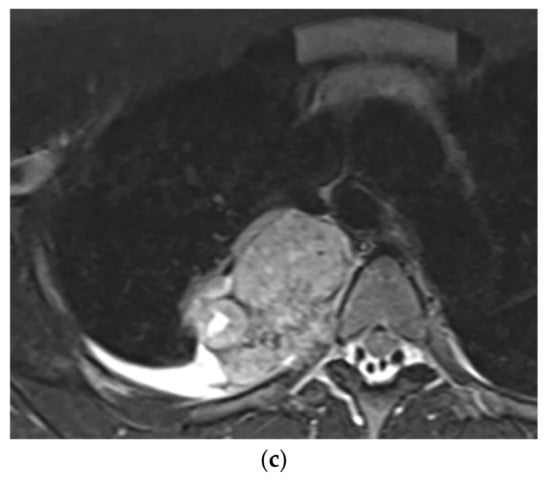

9.1.3. Neuroblastoma

Thoracic Neuroblastoma is a non-encapsulated tumor that arises from extra-adrenal sympathetic ganglia. The mediastinum is the second most common tumor location after the abdomen that has a better prognosis than other sites.

Neuroblastoma appears as an ill-defined paravertebral soft tissue mass on a CT scan with heterogeneous attenuation caused by hemorrhage, necrosis, or cystic degeneration. Internal calcification is seen at least in 30% of cases [7,16]. MRI shows irregular margin with possible local invasion to the spinal canal, presenting T1-hypointensity and T2-hyperintensity with heterogeneous enhancement. Calcification has a signal void in all sequences (Figure 18 and Figure 19). It is reported that tumors with higher metabolic activity on 18F-FDG PET/CT have lower overall survival [44,45]. Metaiodobenzylguanidine labeled as 123I (MIBG) is highly sensitive for detecting catecholamine-producing tumors like neuroblastoma [7,16].

Figure 18.

A 6-year-old boy with posterior mediastinal mass with histopathological confirmation for Neuroblastoma. Axial (a) T2W shows an ill-defined lobulated group (arrow) with heterogeneous and hyper-intense signal intensity and area of a signal void within the posterior mediastinum. It has intracanal extension via right-sided neural foramina and extradural components at multiple levels. It displaced the spinal cord anteriorly, as shown in sagittal T1W after gadolinium administration (arrow) (b).